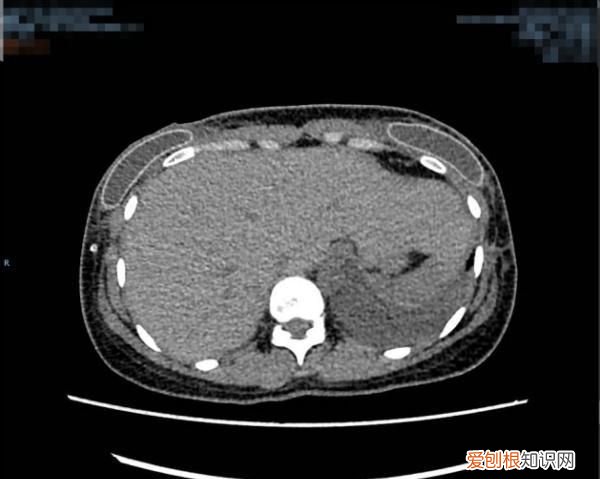

该患者胸部增强CT术前(左图)术后(右图)对比图,其中术前大小约:267mm×100mm×293mm(左),125mm×270mm×340mm(右)